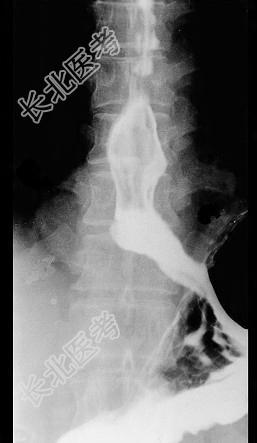

- 单项选择题男性患者,42岁, 2年前始有吞咽梗阻感,近期又出现胸骨后压迫感, 入院行X线钡餐检查,结果如图所示, 最有可能的诊断是 ( )

A、食管癌

B、贲门癌

C、食管憩室

D、食管平滑肌瘤

E、贲门失弛症